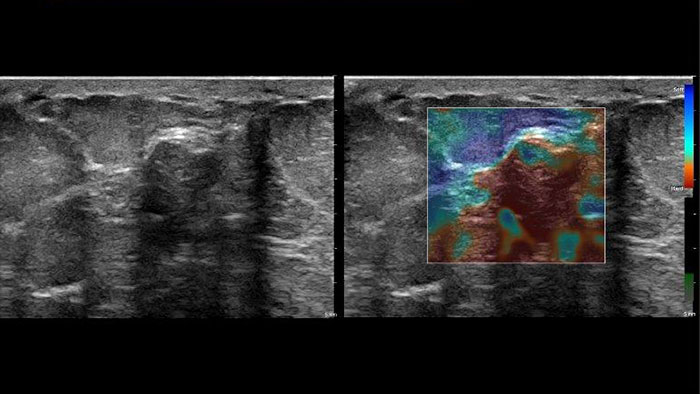

Nowe metody pomiaru sztywności tkanek

Aplikacja US Q-App Elastography Analysis (EA)* pozwala na analizę odkształcenia tkanki na podstawie elastogramu. Można ją stosować w celu porównania rozmiarów dwóch obszarów zainteresowania. Wyniki można dołączyć do dokumentacji pacjenta.

Aplikacja US Q-App Elastography Quantification (EQ)* pozwala na przeprowadzanie oceny ilościowej odkształcenia tkanki na podstawie elastogramu. Użytkownik może wykonywać obliczenia i wyświetlać informacje na temat szybkości odkształcania i odkształcenie całkowite, wyniki porównania rozmiarów dwóch obszarów zainteresowania oraz współczynnik odkształcenia. Dane te można dołączyć do dokumentacji pacjenta.